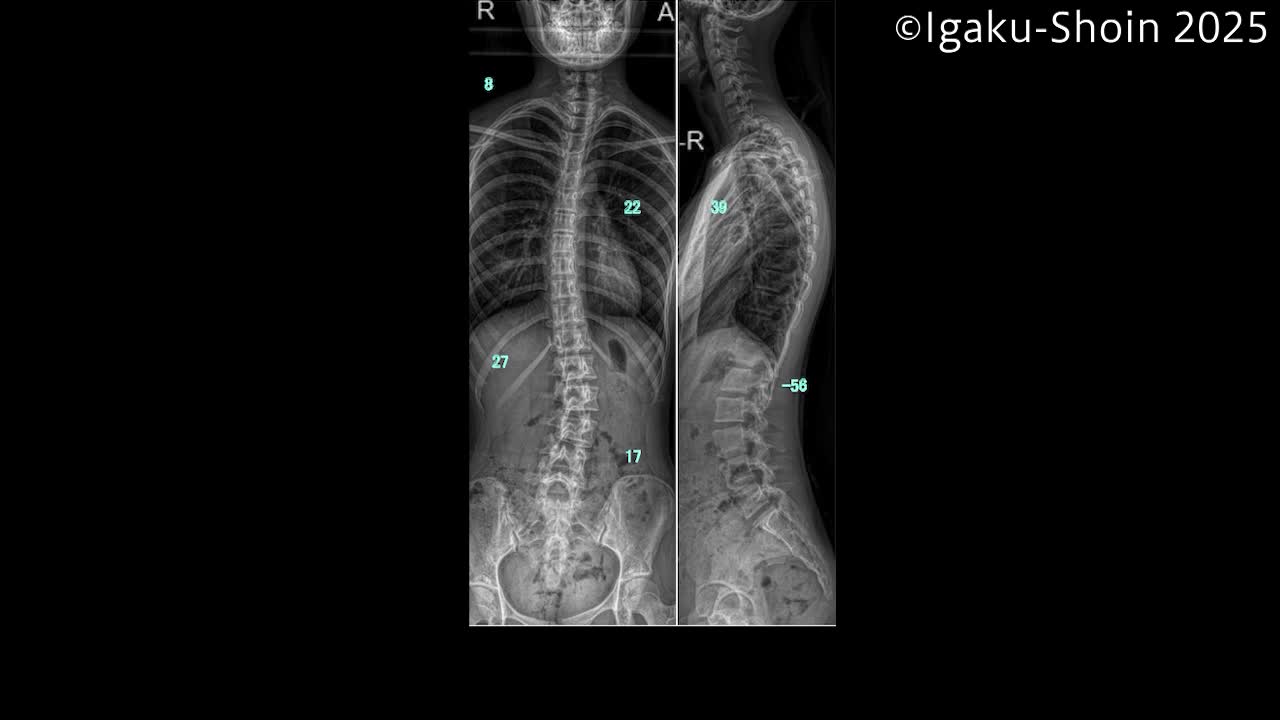

• 動画38 Corrective PLIFの手術

動画38 Corrective PLIFの手術 00:10:00